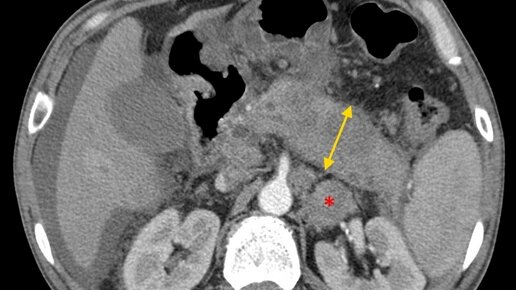

Компьютерная томография поджелудочной железы является неинвазивным методом лучевой диагностики данного органа. Она позволяет быстро визуализировать патологические изменения поджелудочной железы, клетчаточных пространств и других органов живота. В диагностических центрах ее проводят в рамках нескольких протоколов: Нужный способ обследования обычно выбирает лечащий врач и указывает в своем направлении на диагностику. ПОКАЗАНИЯ Сложность дифференциальной диагностики опухолевых и воспалительных поражений...